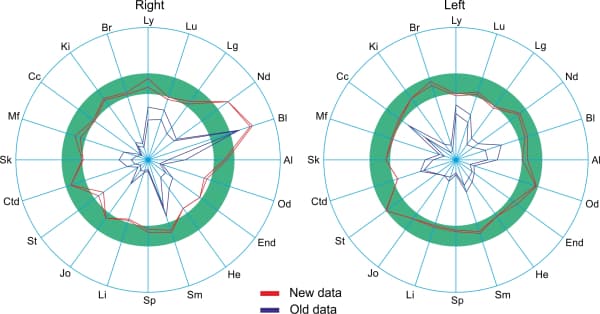

The following depicts the total deviation from the norm from the right (Fig. 1) and from the left (Fig. 2), under the influence of an Aires Defender.

The subject has a pronounced asymmetry in the initial measurements: 33 from the right and 44 from the left, which indicates a desynchronization of the right and left cerebral hemispheres.

After 46 hours of using the Aires Defender, the value dropped on both sides to 22 and the asymmetry was gone. After 98 hours of using the Aires Defender, the value dropped to a minimum of 5 on both sides.